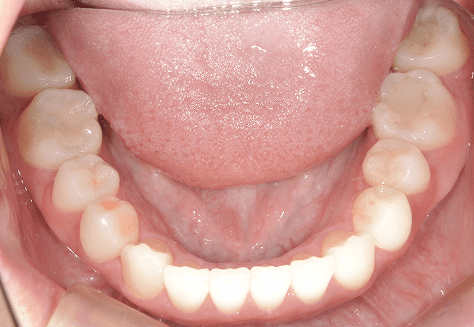

M.U

治療前

治療後

主訴

下の歯が特にガタガタなのが気になる。上の前歯が1本反対になっている。

診断

下顎前突・叢生・反対咬合

年齢/性別

20代/男性

抜歯部位

非抜歯

使用装置

上下インビザライン(PBM使用)

保定装置

ビベラリテーナー

基本料金

950,000円

診察料金

5,500円×16回

治療期間

1年7カ月